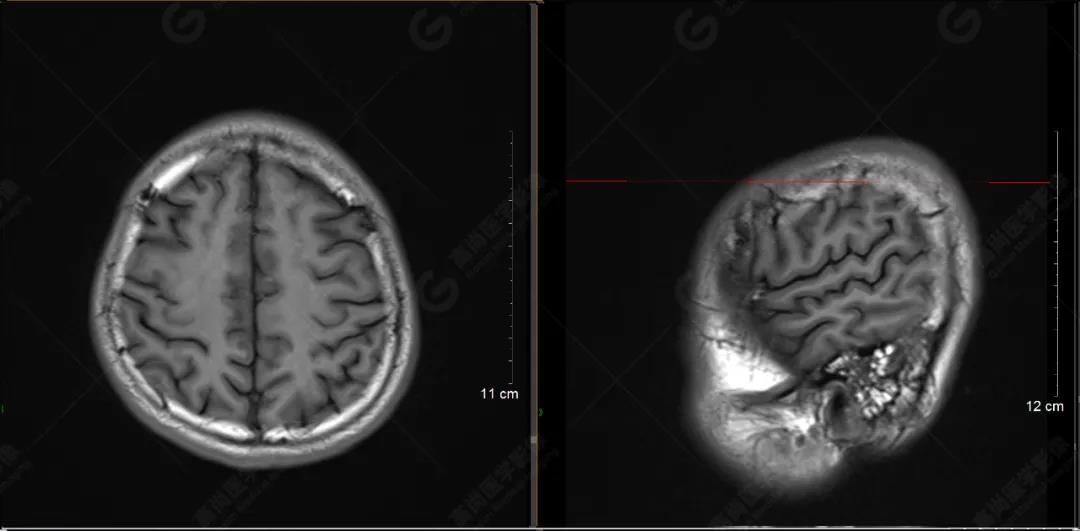

以下是平掃T2WI及FLAIR序列:

雙側(cè)大腦半球?qū)ΨQ,灰白質(zhì)對比正常,顱內(nèi)未見異常信號影。腦室系統(tǒng)未見擴(kuò)大,中線結(jié)構(gòu)居中。腦溝、裂未見增寬。幕下小腦、腦干未見異常。矢狀位示垂體形態(tài)、大小級信號未見異常。所示左側(cè)乳突內(nèi)見多發(fā)短T1長T2信號影。

顱腦MRI平掃未見明顯異常,左側(cè)乳突內(nèi)積血,建議補充SWI檢查。